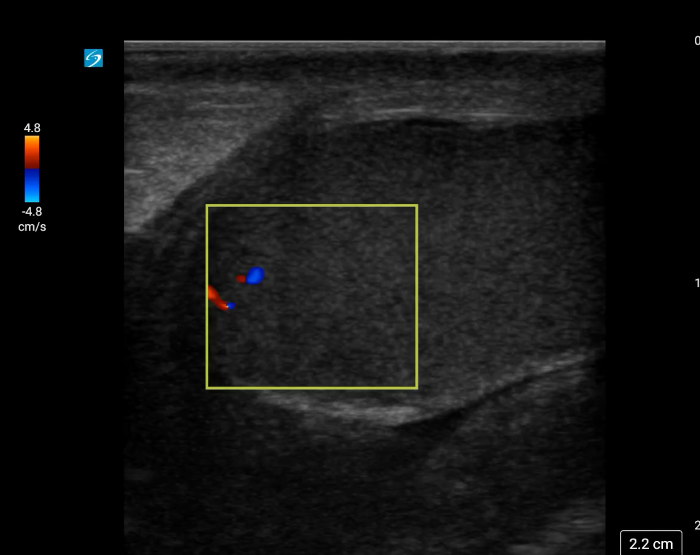

In your first image (Image 1), you realize there is no flow with color Doppler. Additionally, you find a torsed cord complex (Image 2), also known as the “corkscrew sign.” You consult Urology who is busy in the operating room with another case. You decide to perform a manual detorsion due to your concern for testicular atrophy and risk of infertility. Using the open book technique, you get relief of pain and return of vertical positioning of the testicle after two rotations. On your repeat testicular POCUS with color Doppler you obtain these images (Images 3 and 4), which demonstrate venous and arterial flow throughout the testicle. The cord is now untwisted and appears linear in orientation.

Torsion - image 3_crop.pngImage 3. Color Doppler demonstrating intratesticular flow toward and away from the probe.